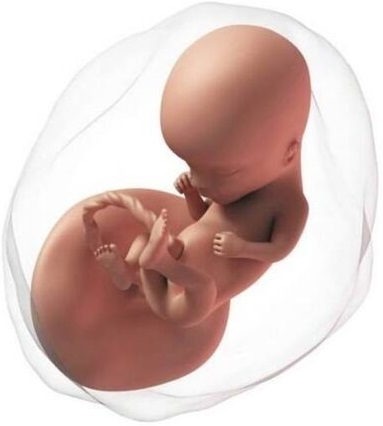

El proceso de la formación del embrión está ya prácticamente finalizado con una longitud de 30 mm. A partir de ahora empieza la etapa fetal, médicamente ya no es un embrión sino un feto. Ya ha completado la formación básica de todos los sistemas.

Ahora ya se mueve con frecuencia, pero son movimientos involuntarios; los músculos todavía tardarán en estar conectados con el cerebro. La cabeza es mucho más grande que el cuerpo, ya tiene orejas, nariz, hasta los párpados, los cuales estarán fusionados durante semanas. Los labios están formados y empieza a abrir la boca. Ya han aparecido pies y manos.

En esta etapa los genitales son exactamente iguales en niños y niñas. Tienen un tubérculo genital que más adelante se diferenciará en la forma de cada sexo. Su piel es translúcida, se puede ver el esqueleto a través de ella. En realidad, los huesos no tienen casi calcio, están formados por cartílago, pero la mayoría de los huesos ya tienen su forma definitiva.

Es cada vez más parecido a un bebé, con la cara más redondeada. Su tamaño es aproximadamente 30 y 40 mm. Los huesos ya acumulan calcio.

En la cabeza, miles de neuronas se crean cada día y hacen que el cerebro se desarrolle rápidamente. Es fundamental que se formen adecuadamente; más adelante viajan a diferentes partes del cuerpo y se conectarán entre ellas. Las manos ya se abren y cierran de forma periódica. Los intestinos siguen formándose. La barriga del bebé en pocos días ya tendrá el aspecto que tiene la de un recién nacido, con el cordón umbilical entrando por el ombligo.